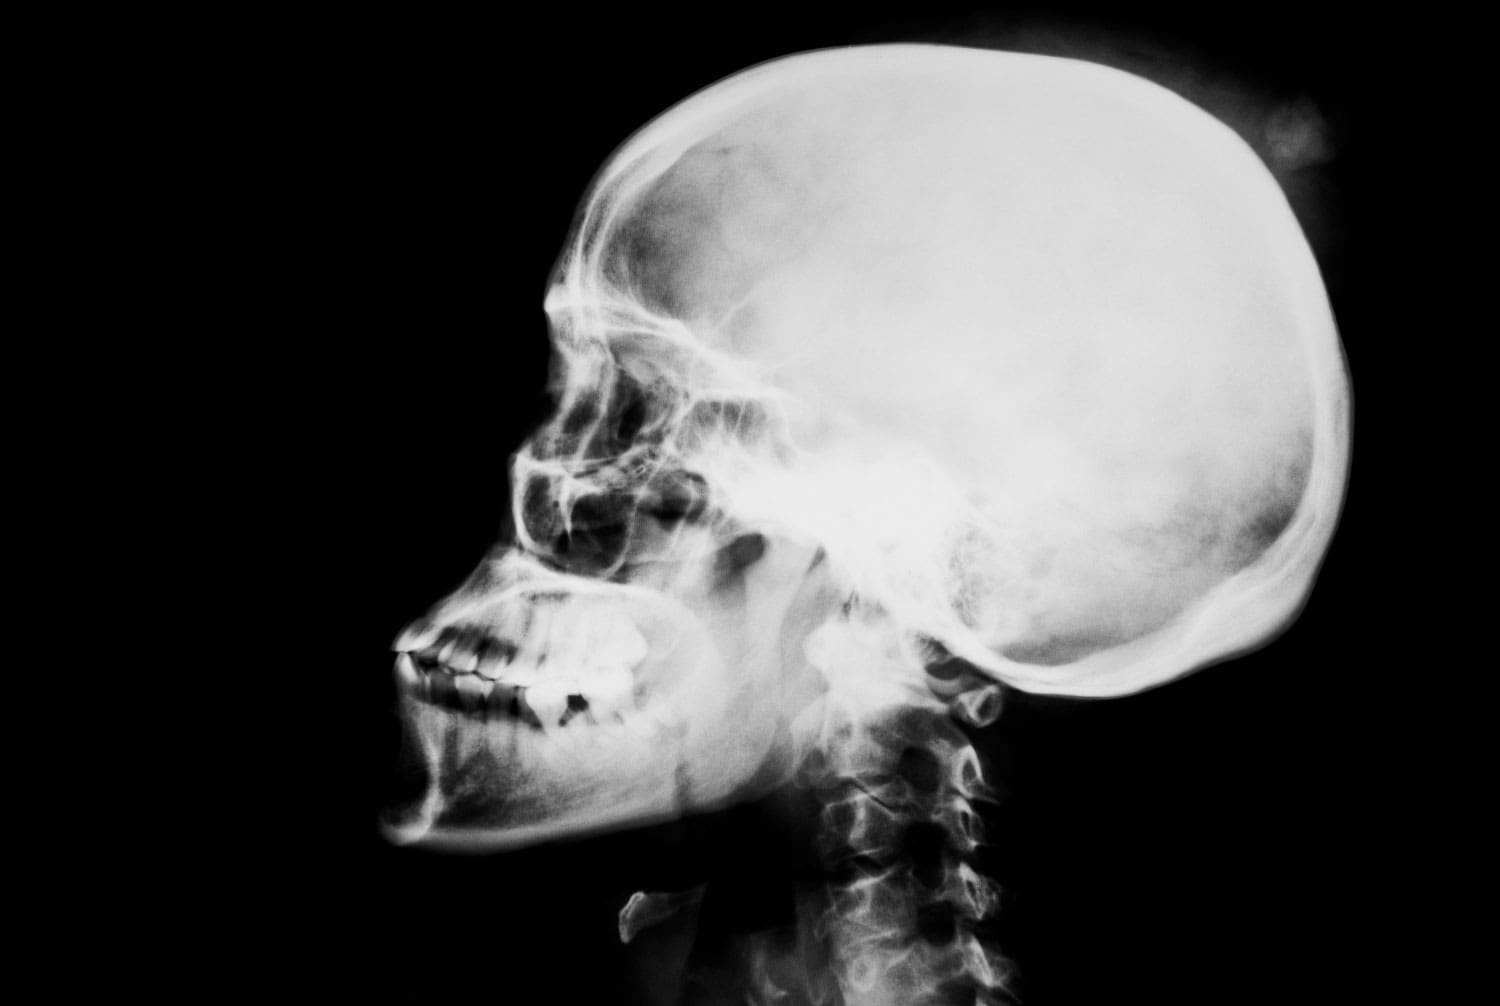

Las Lesiones Cerebrales Traumáticas (LCT) han sido recientemente objeto de una gran película de Hollywood, numerosos perfiles de noticias, audiencias en el Congreso y debates aparentemente interminables en televisión.

Las lesiones cerebrales pueden causar una amplia gama de síntomas, muchos de los cuales pueden conducir a la pérdida del empleo, cambios de personalidad y graves episodios de depresión.

Los síntomas pueden incluir – Mareos y falta de equilibrio – Deterioro de la memoria – Náuseas y vómitos – Pérdida del sentido del olfato o del gusto – Zumbidos en los oídos – Dificultad para recordar, concentrarse o tomar decisiones.

– Lentitud para pensar, hablar, moverse y leer.

– Perderse o confundirse fácilmente, incluso en lugares familiares – Sentirse cansado todo el tiempo – Menor energía o motivación – Cambios de humor que pueden parecer irracionales – Cambios drásticos en los patrones de sueño – Mayor sensibilidad a las luces, los sonidos – Visión borrosa En algunos casos, los síntomas pueden ser incluso peores, pero en todos los casos recibir el mejor tratamiento y plan de recuperación es la clave para volver a encarrilar tu vida.